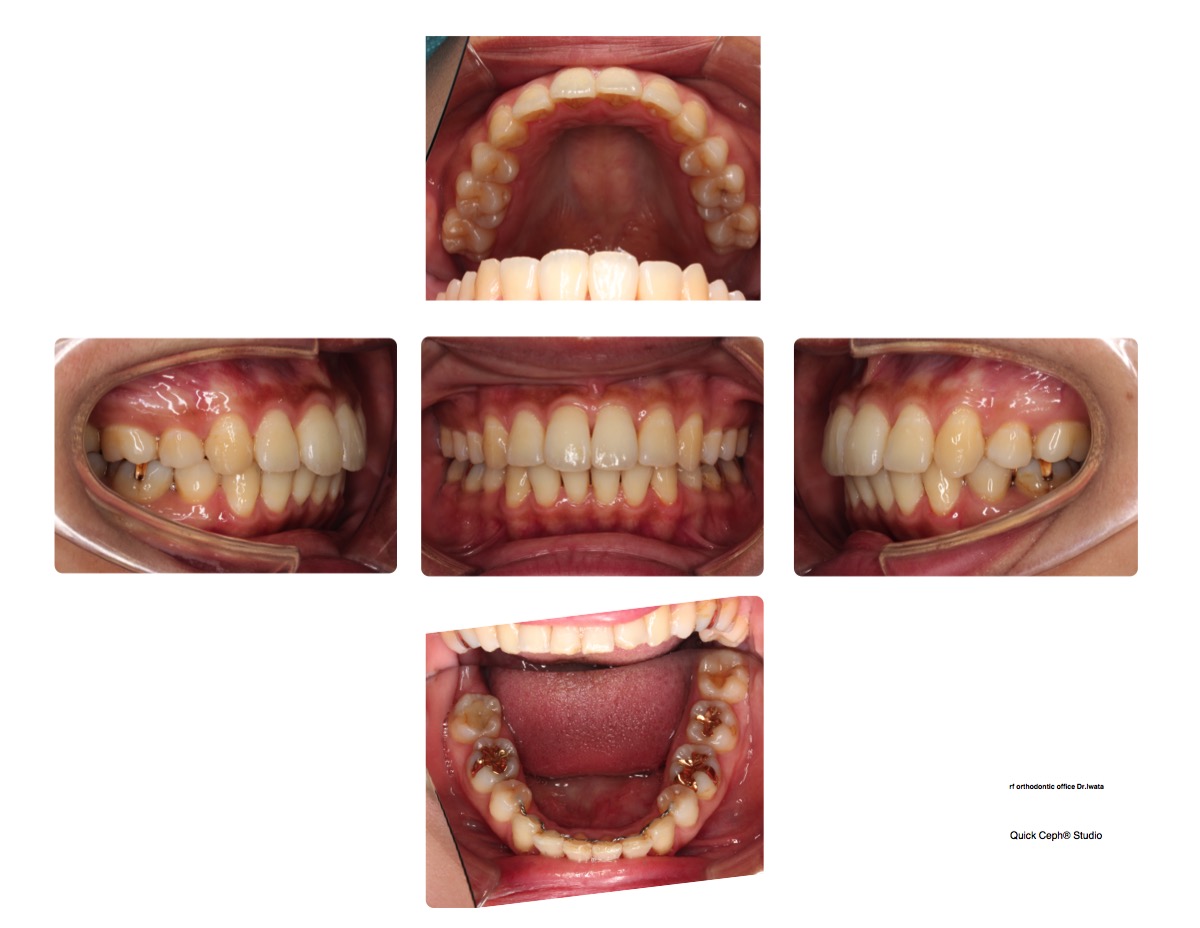

そこで久しぶりに治療前後の歯並びの写真を先生に見せてもらって。。。

やっぱり全然違う!!!

ほんとに矯正してよかったなあと思うこの頃。

先生にも話したけど昔の写真を見ると笑い方も歯並びが見えないようにしてたし。

今は前歯めっちゃ見せて笑えてます。